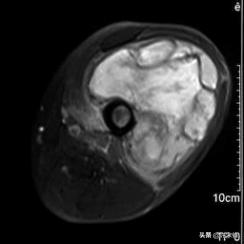

MRI检查时,T1WI表现为和软组织等信号或接近等信号,T2WI表现为高信号,如有坏死表现为更高信号区,如有出血,在T1WI、T2WI上均表现为高信号,增强后有强化表现。

男,65岁,左大腿横纹肌肉瘤,侵及左股骨